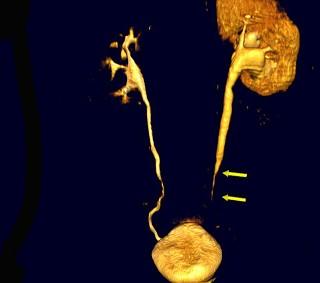

问题 男,59岁,反复尿频尿急尿痛4年余,尿常规检查:红细胞(+),白细胞(++),CT扫描如图示,下列说法正确的是 ( )

选项 A、考虑为慢性输尿管炎 B、考虑为输尿管移行细胞癌 C、左侧侧输尿管上段扩张 D、考虑为输尿管结核 E、左侧输尿管中下段输尿管管壁增厚,管腔狭窄

答案 ACE